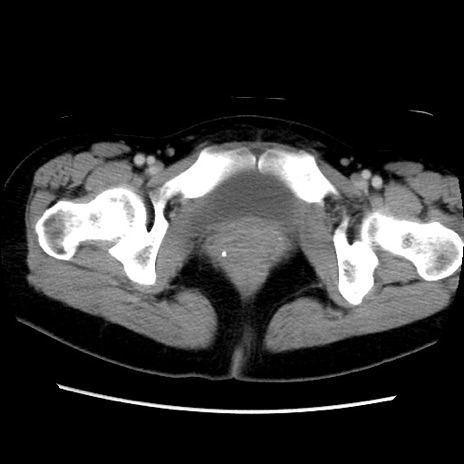

MRI(4日後)

【症例】40歳代女性

【主訴】上下腹部痛

【現病歴】2日目から下腹部痛あり。夜間は痛みで眠れなかった。昨日より上腹部痛と下痢が出現。臥位で痛みは軽快したため、休んでいた。本日になって臥位でも立位でも痛みが強くなってきたため救急要請。

【既往歴】子宮内膜症

【身体所見】部:平坦・軟、左上下腹部に圧痛あり、反跳痛あり。

【データ】WBC 21800、CRP 26.78